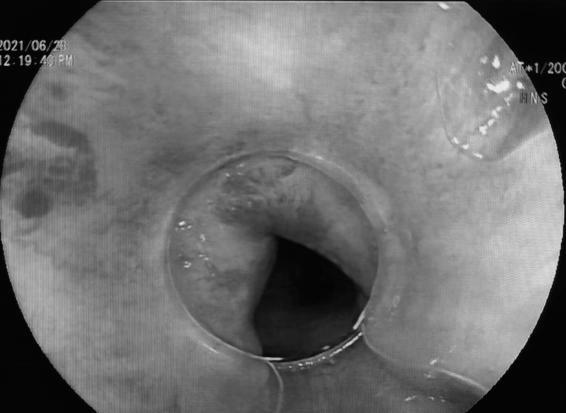

患者术前和术后内镜对比

术后内镜下直肠曲张静脉